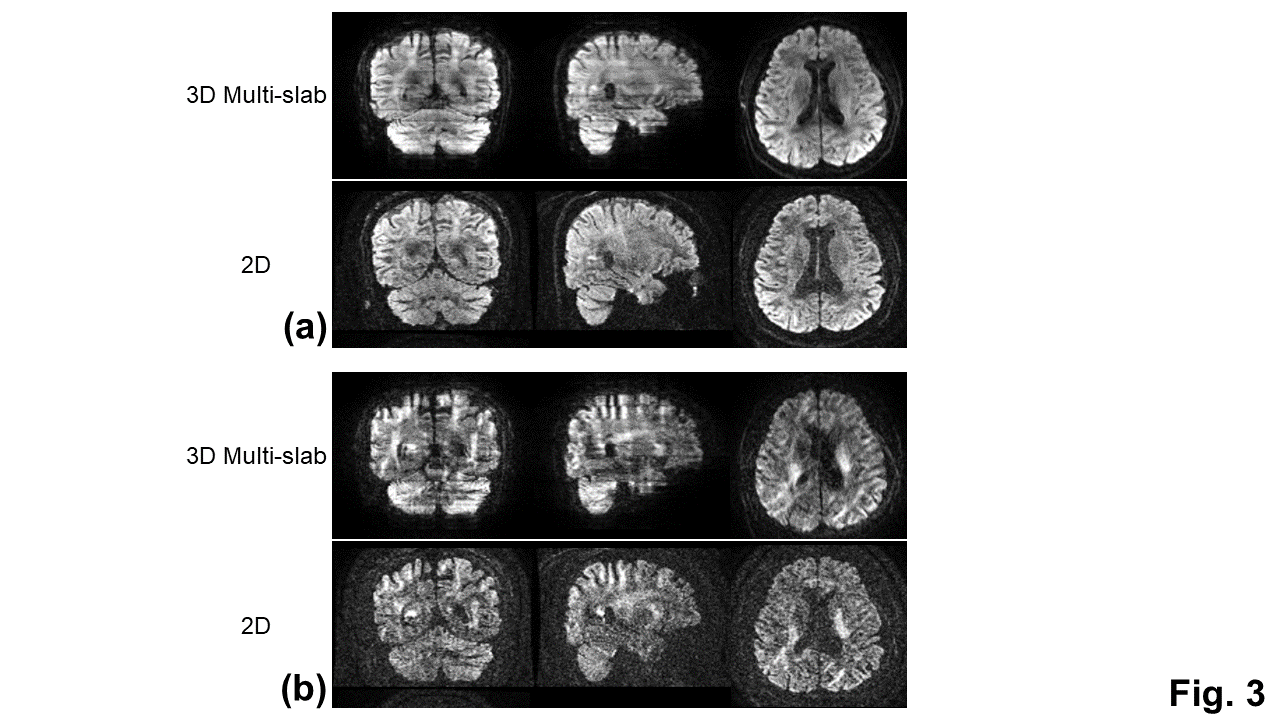

With the phase correction, the signal drop in DWI images was mitigated (Fig. 1b). The remaining slab boundary artifacts were reduced by using NPEN for combining slab images (Figs. 1a and 1b). Following the phase correction and NPEN, the 3D multi-slab DWI images for DTI measurements were used to generate color-coded FA maps (Fig. 2). For DKI measurements, the 3D multi-slab DWI images showed a higher SNR than the 2D DWI images (Fig. 3). The benefit of SNR was demonstrated by the mean kurtosis maps (Fig. 4). The mean kurtosis maps obtained by the 3D multi-slab DWI were more smooth in white-matter regions than those obtained by the 2D DWI. However, many zeros (negative kurtosis) were present on the mean kurtosis maps mainly at the gray matter–white matter and gray matter–CSF interfaces, likely caused by the partial volume effects. In the 3D multi-slab DWI, negative kurtosis may also result from the procedure for correcting the motion-induced phase errors. The self-navigation correction method17 relies on the smooth phase differences between b0 and DWI images to estimate the motion-induced phase. The choice of the smoothing kernel may result in incomplete removal of the phase errors or undesirable removal of the phases related to structural variations9,20,23. Future work is to increase the image resolution to reduce the partial volume effects and structure-related phases, and allow a more complete removal of the phase errors.

Fig. 3: Comparisons of DWI images obtained by the 3D multi-slab DWI and 2D DWI for the DKI measurements with the identical image resolution and scan time. DWI images with b = 1000 s/mm2 (a) and 2500 s/mm2 (b) along a single diffusion encoding direction.